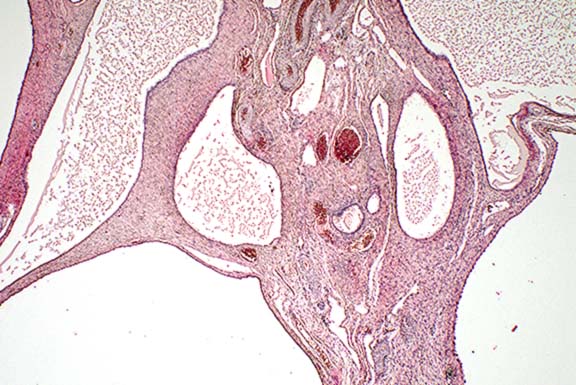

Contributor's Diagnosis and Comments: Cystic rete ovarii.

Multiple cysts of variable diameter (up to 2 cm) displacing the ovarian parenchyma are visible. The cyst lining varies from single to several layers of flattened to cuboidal epithelium. Some of the cysts are lined by cuboidal ciliated epithelium. Several cysts are filled with proteinaceous fluid. Occasionally folds which protrude into the cyst lumen and contain a blood vessel in the apical part can be observed.

In cats, as in other mammals, the rete ovarii consists of three parts: an intraovarian rete system, a connecting rete system, and an extraovarian system. The intraovarian rete is located in the ovarian medulla and is lined by cuboidal epithelium. At the tubular extremity of the ovary, the intraovarian system becomes a reticular formation of dilated tubules lined by ciliated columnar epithelium- the connecting rete. The extraovarian rete consists of tubules composed of ciliated columnar cells extending from the connecting rete and ending blindly in the periovarian tissue. Cysts of the rete system have been described in different species including cats. The epithelial lining of the cyst walls can vary from single to several layers of cuboidal or flattened to columnar and ciliated epithelial cells.

Conference Note: Cysts of the ovarian rete are only one of sixteen different types of cysts occurring in and around the ovary of domestic animals.3 The incidence and relative significance of these is variable among animal species. In the cow and sow, follicular cysts are most frequent, and are important causes of infertility. These occur less frequently in the bitch and queen. Cats with follicular cysts may show signs of hyperestrogenism. On the other hand, cystic rete ovarii are most common in the bitch and queen, and seldom if ever cause clinical signs.

Histologic differentiation of the various types of cysts can

be difficult. Important features include the type(s) of epithelium

lining the cyst, presence or absence of smooth muscle in the wall

of the cyst, and anatomic location.